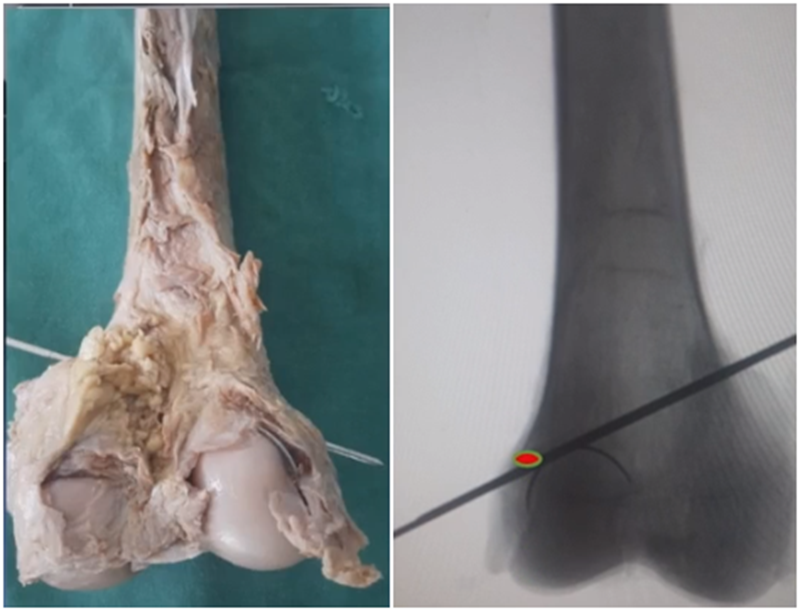

(1)合页骨折

对于术中出现的合页骨折,此时还有一定的稳定性,可以调整力线固定以后,由前外向后内打一根防旋螺钉,这样仍然是比较稳定,术后康复计划与正常一样。

对于术中合页骨折,但非常不稳定、无法控制力线的情况,可以由外侧向股骨外髁打入一枚2.0的克氏针,因为克氏针具有一定弹性,相当于重建合页临时稳定性,在此基础上再去调整力线,做固定。

术后做植骨,早活动、晚负重,避免做扭转活动。

晚期出现的合页骨折,此时力线已经改变,只能进行翻修。